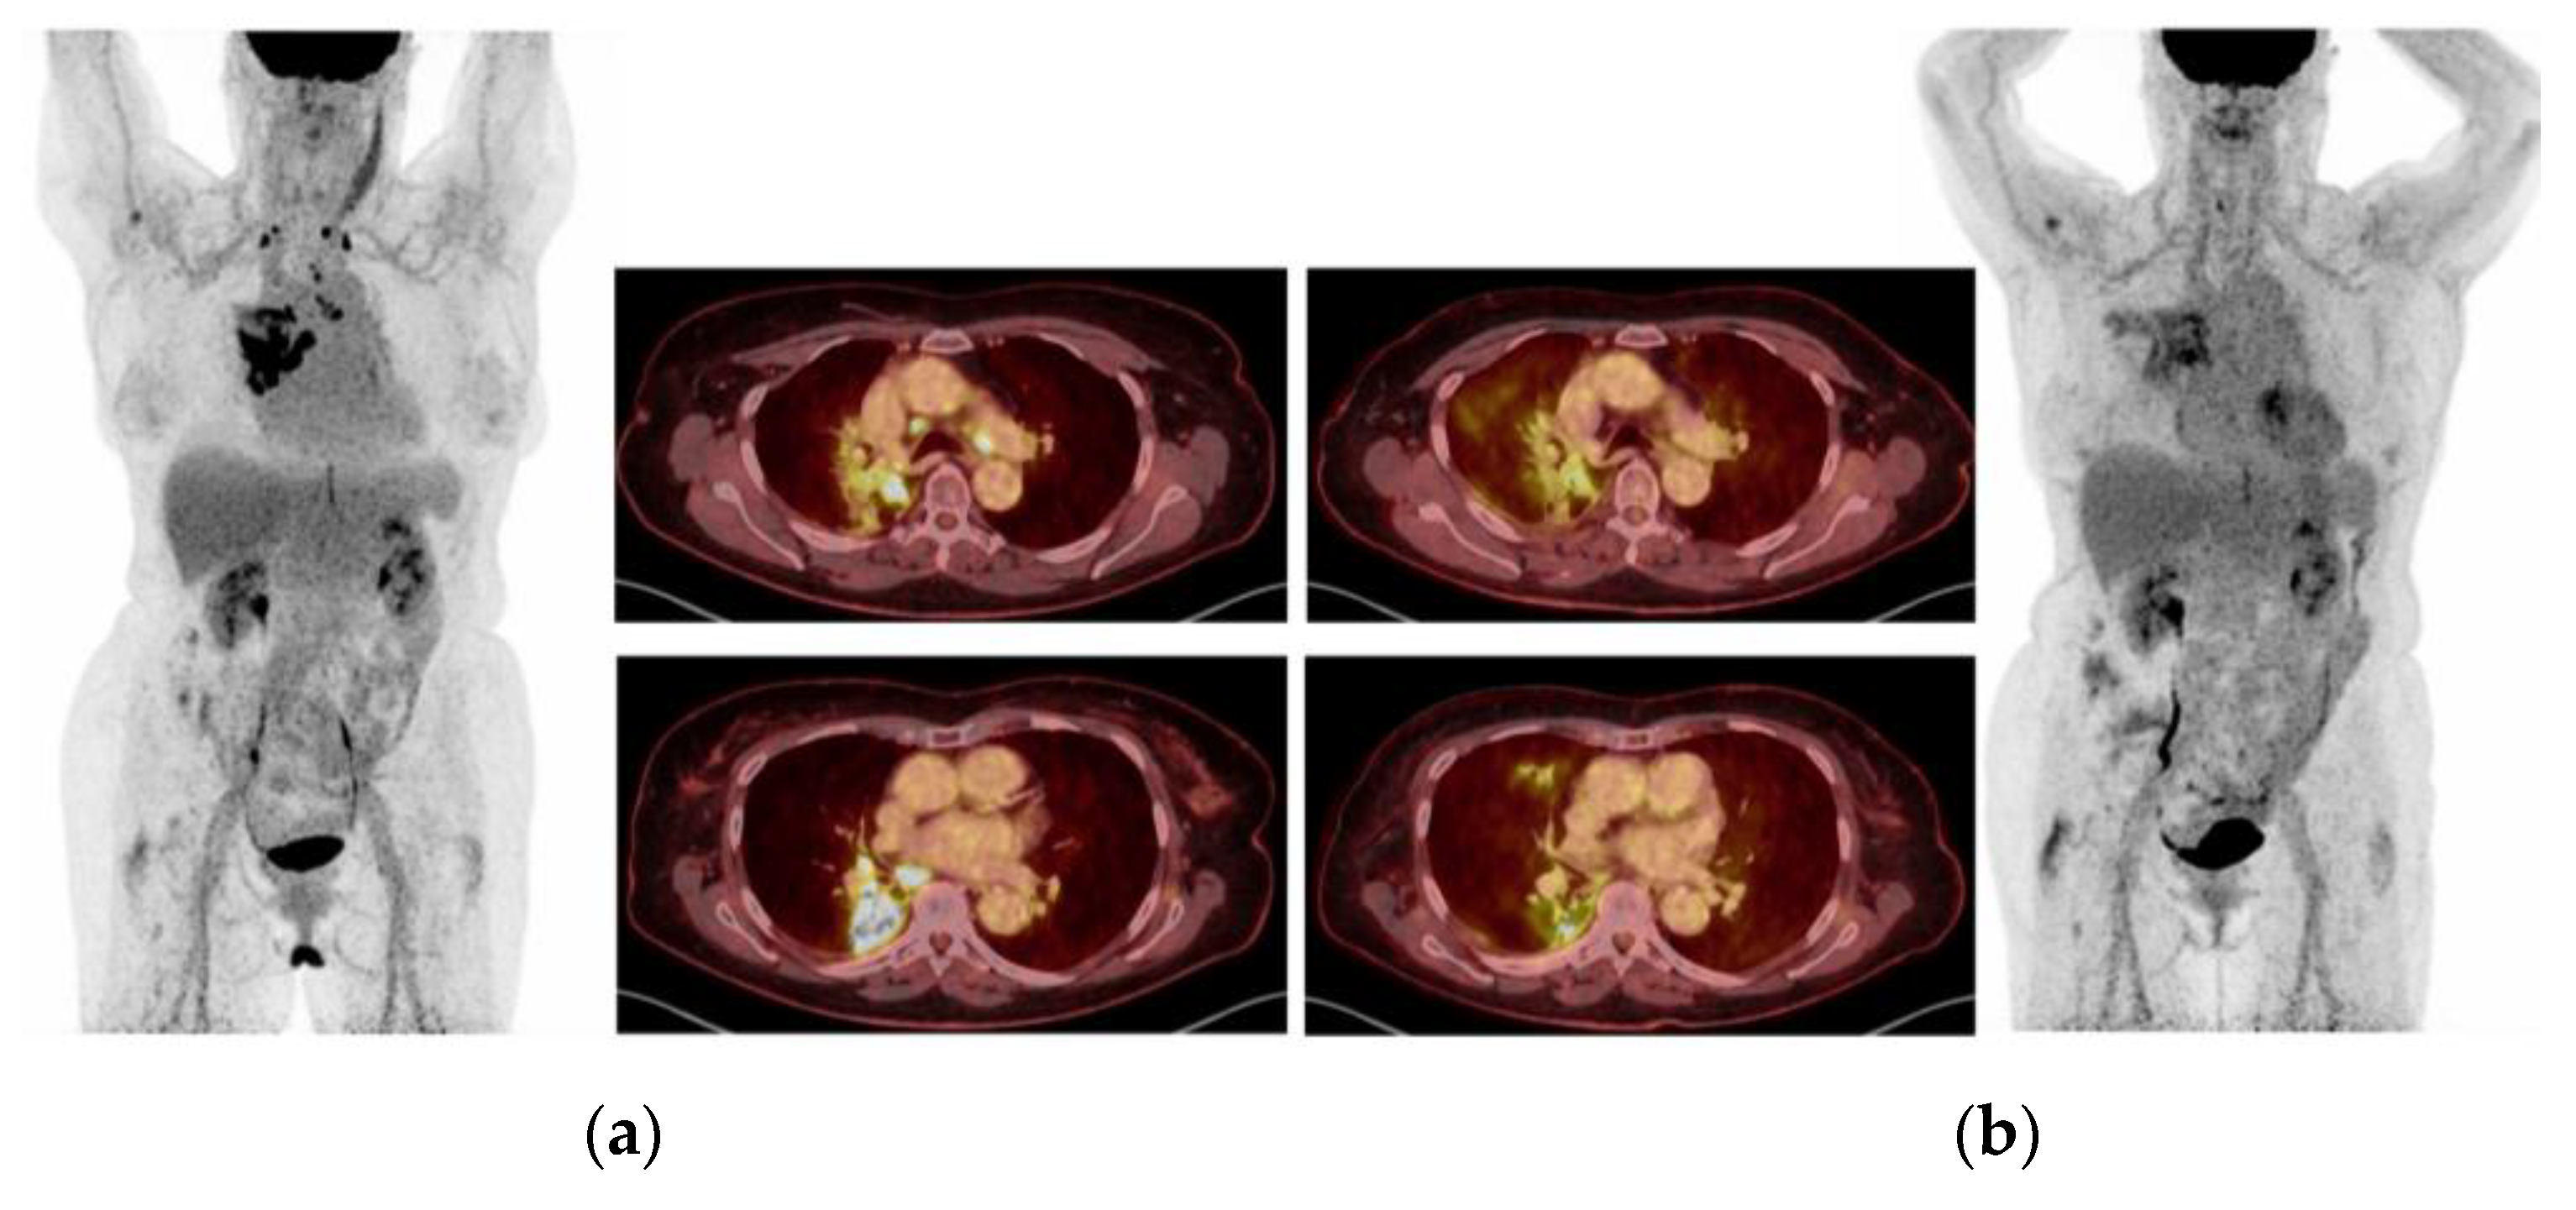

2.1. Case 1: Metastatic NSCLC with EGFR ex19del and Acquired MET Amplification: Short-Term Complete Response (CR) by Combining Crizotinib with Osimertinib

2.5. Case 5: Efficacy of Crizotinib-Osimertinib in EGFRm+ NSCLC Patient Acquiring High-Level MET Amplification after 26 Months of Treatment with Osimertinib